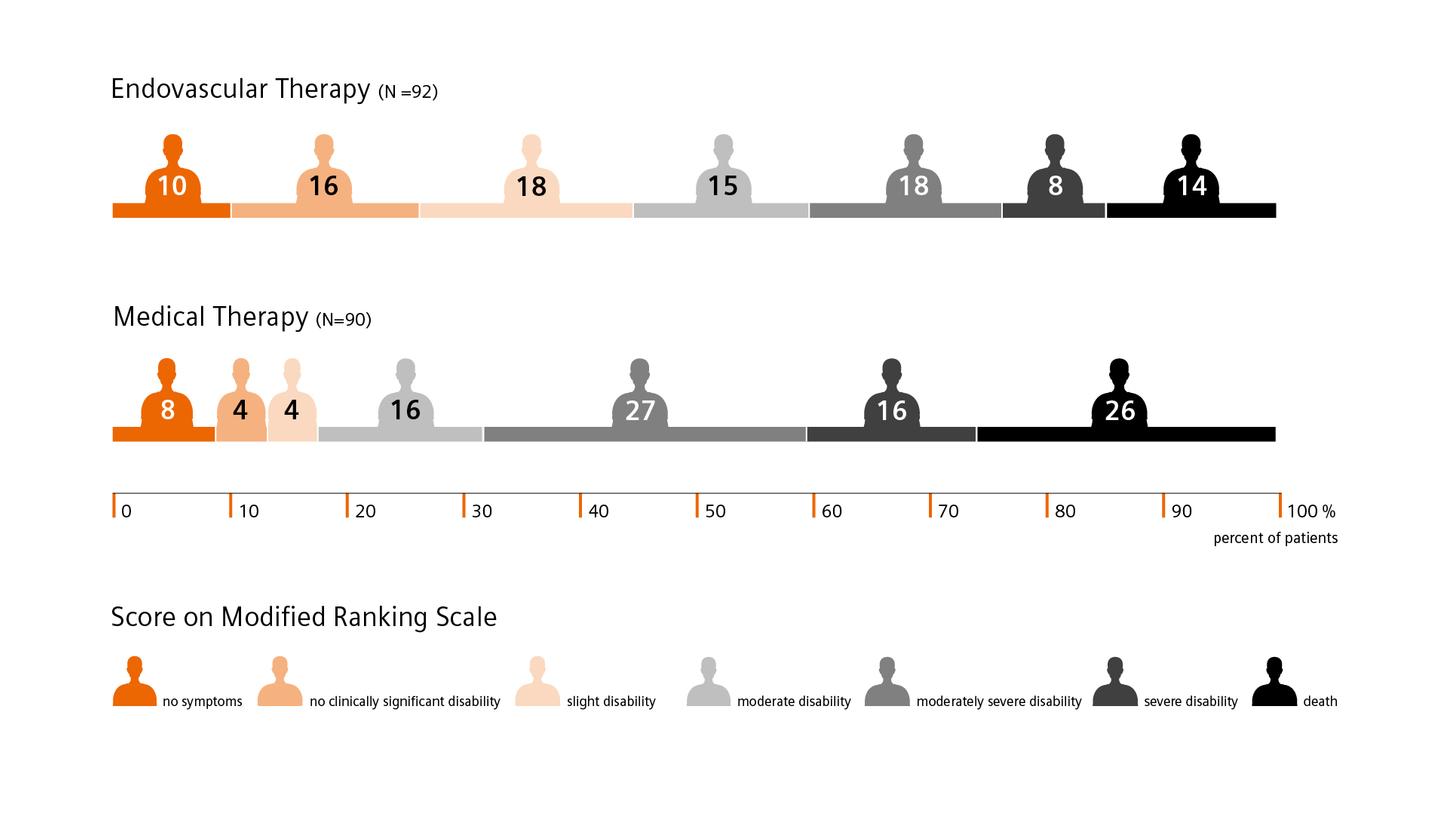

DEFUSE 3 shows favorable outcomes for late-window patients. For example: Mortality rate was 14% in the endovascular therapy group, compared to 26% in the medical therapy group. And there was no significant between-group difference in adverse events.4

DEFUSE 3 shows favorable outcomes for late-window patients. For example: Mortality rate was 14% in the endovascular therapy group, compared to 26% in the medical therapy group. And there was no significant between-group difference in adverse events.4